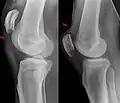

Quadriceps tendon rupture in plain X-ray -

Quadriceps tendon rupture in plain X-ray: Incomplete rupture with haematoma in tendon. -